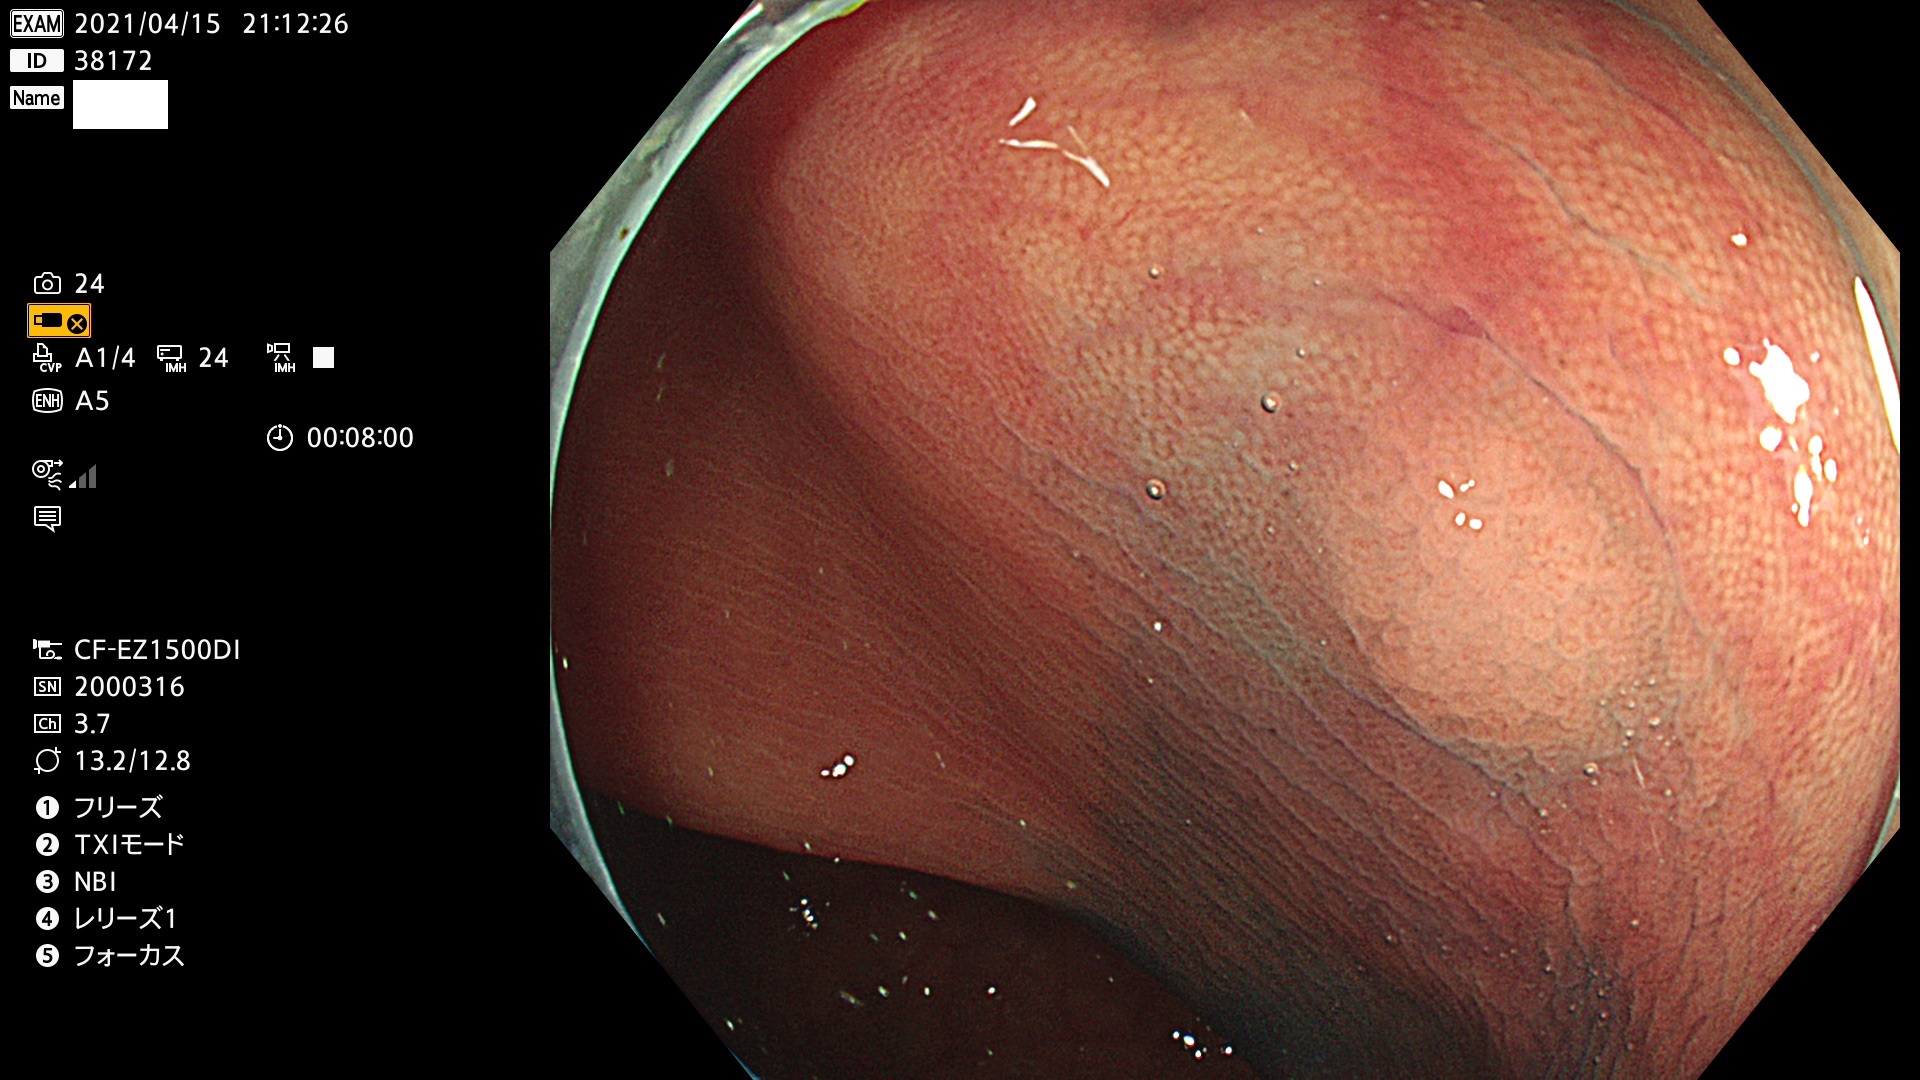

腺腫発見率 72 % (カルテ番号 38100〜38199の100名の方の検査結果で集計)大腸癌検診最新情報

以下のカルテ番号の方に腺腫(Adenoma,Group3〜5)が見つかりました(集計法)

38101 38103 38104 38106 38107 38108 38109 38110 38111 38112 38113 38114 38115 38117 38118 38122 38123 38124 38125 38126 38127 38128 38130 38131 38132 38135 38137 38138 38140 38141 38142(SSAPのみ) 38143 38144 38145 38146 38147 38148 38149 38150 38151 38152 38153 38154 38157 38158 38160 38161 38162 38164 38165 38166 38167 38168 38169 38172 38176 38177 38178 38181 38182 38183 38184 38187 38189 38190 38191 38192 38193 38194 38195 38196(SSAPのみ) 38198

発見困難で危険性の高い平坦型病変(上記100名より抽出) ![]()